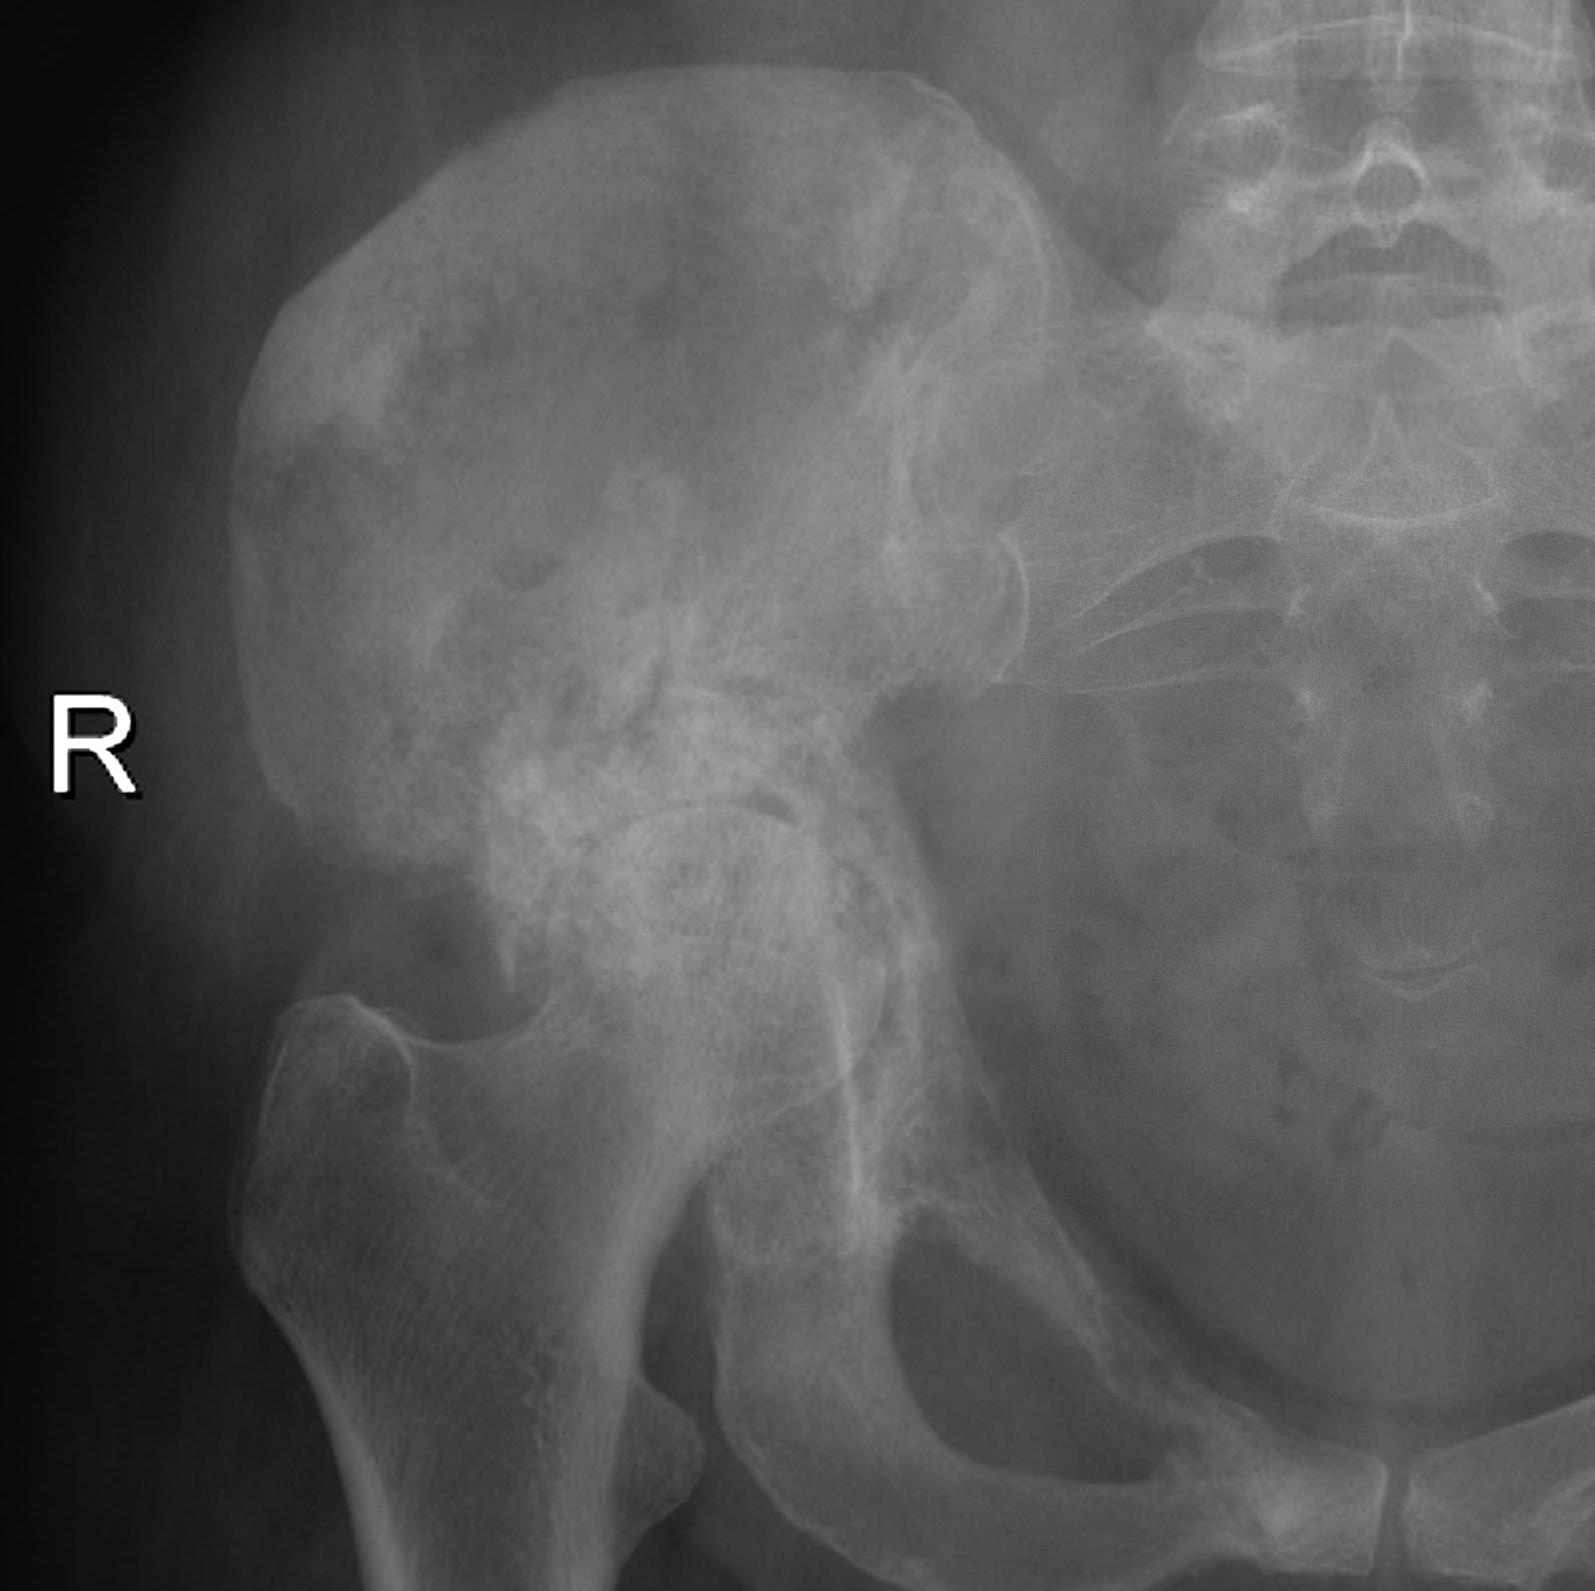

Pelvis

Ewings pelvisAcetab Met

Iliac crest Ilioinguinal approach

Anterior column Watson - Jones through G medius

Posterior column Kocher - Lagenbeck through G maximus

Pubis Pfannenstiel approach

Ischium Posterior approach

Sacrum Direct posterior approach